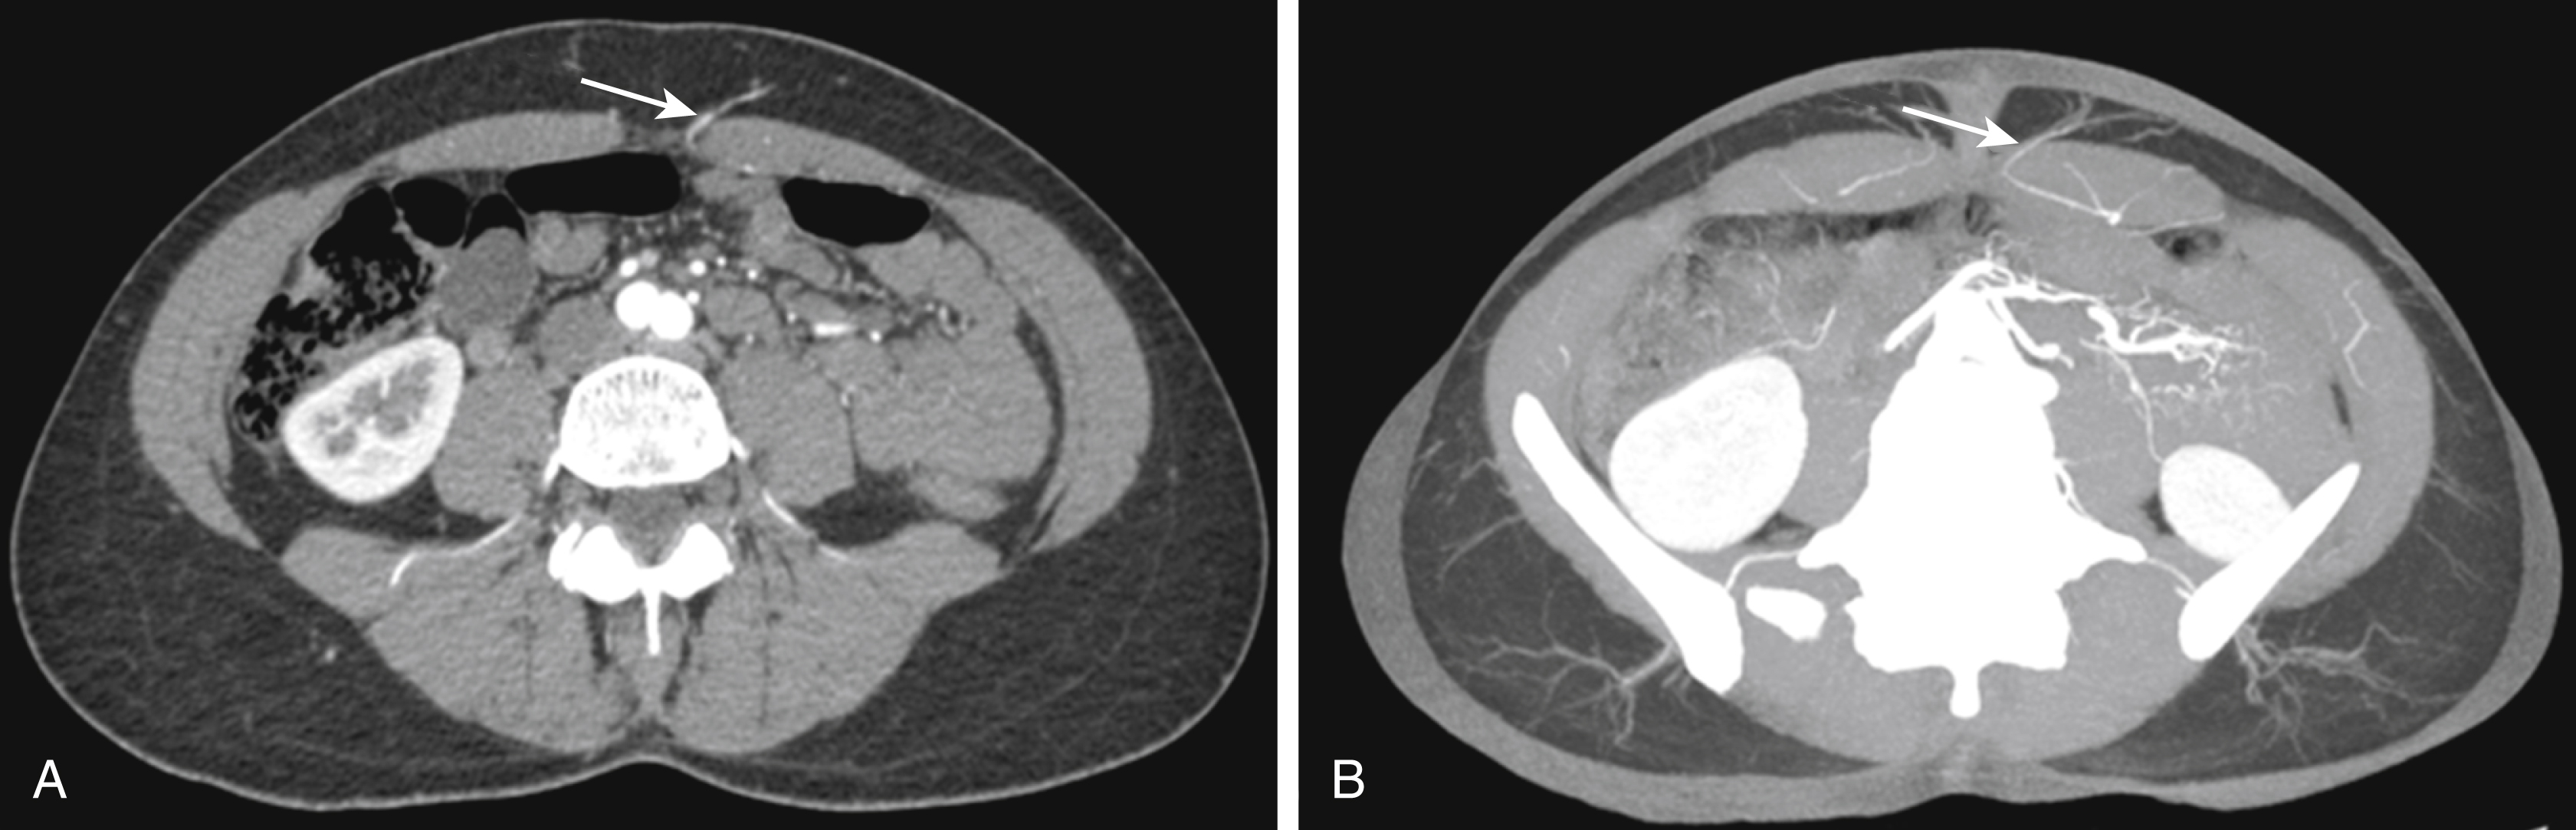

The DIEP flap is the natural evolution of the muscle-sparing flap. In this procedure, the perforating vessels that perfuse the skin are dissected free from the rectus muscle, and the innervation of the muscle is largely maintained. The size and location of the abdominal wall perforators can be assessed preoperatively using computed tomographic angiography (CTA) or magnetic resonance angiography (MRA) ( Fig. 36.6 ). This information may enable the surgeon to assess the feasibility of performing a DIEP, decrease operative time, and provides an estimate of the amount of tissues available for breast reconstruction. The position of the perforators is usually marked in relation to the umbilicus, and the flap is designed to capture the largest perforators. In some cases, however, preoperative imaging may not be available, and the procedure can simply be performed by surgically exposing the perforators and selecting the best option for reconstruction. The use of a handheld Doppler may help identify perforators preoperatively in these cases; however, in general, this is not necessary.